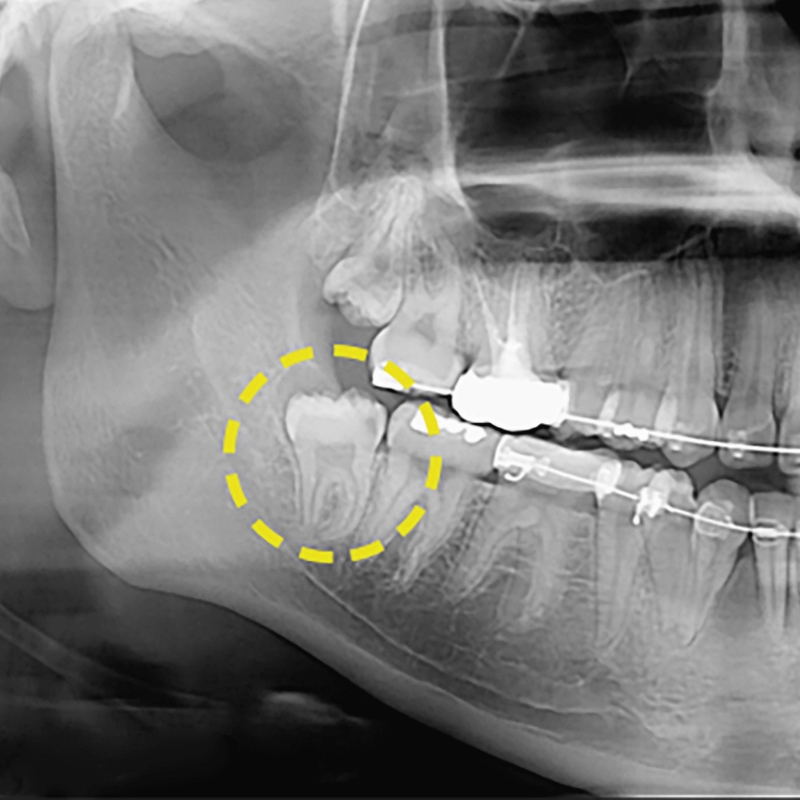

매복사랑니는 치아의 맹출이 이루어지지 않고 사랑니가 잇몸 밖으로 나오지 못해 누워있거나 숨은 상태를 보이는 치아를 이야기해요. 보통 턱뼈의 크기가 작아 치열가 배열된 공간이 부족하거나 치아의 배열이 올바르지 못할 경우에 발생을 하는데요. 평소에 맨 눈으로 쉽게 확인을 할 수 없으며 일상생활에 있어 불편함을 느끼게 하거나 통증과 염증을 유발하기도 했었어요. 아름드리치과에 내원한 환자분의 경우 정상적이지 않는 각도로 자리잡은 매복사랑니발치를 하지 않은 경우에는 주변 치아의 신경을 건드리며 자랄 수 있어 인접치에 안 좋은 영향을 줄 수 있었어요. 특히 비스듬하거나 누워 자라는 매복 사랑니는 잇몸에 염증을 유발하여 치열에 문제를 일으킬 수 있었어요. 치아 머리만 나와 있는 매복 사랑니의 모습이라면 제대로 구강 관리를 하기 힘들어 음식물이 고이기 때문에 치주염과 치아 우식증, 구취등의 문제도 발생하게 되는데요. 컨디션의 저하에 따라 잇몸이 붓고 매복사랑니통증이 느껴지기도 한다면 발치가 효율적일 수 있겠어요.

아름드리치과에서 말하는 매복사랑니발치는 환자마다 맹출 형태가 다르기에 더욱 신중하게 접근해야하는 수술이었어요. 매복되어 있는 정도에 따라 뽑는 방식에도 차이점이 생기기 때문이에요. 치아의 머리가 일부분만 들어가 있는 단순 매복의 경우에는 잇몸만 절개하여 발치를 진행하고 잇몸 안에 부분적으로 치아 머리가 숨어있거나 골 안에 묻혀 있는 복합 매복사랑니라면 잇몸 절개와 더불어 치아를 분리하여 발치를 진행해 주어야 했었어요. 완전 매복의 경우에는 매복사랑니발치 가운데 가장 고난이도라고 보는 수술이에요. 매복된 깊이가 깊기 때문에 정확한 검진을 기반으로 복잡한 단계를 거쳐 빼내야 하고 치아를 조각 내어 분리해야 하는 경우도 발생할 수 있었었어요. 골 삭제도 필요하기에 발치 과정에서 여러 치과 시술을 동시에 진행하는 것으로 아름드리치과와 같은 임상 경험이 풍부한 병원에서 진행하시는걸 추천드려요. 매복사랑니는 치신경에 인접해 있기 때문에 일반적인 사랑치를 발치하는 것보다 더 까다롭게 진행되는 시술이었어요. 발치 시 신경을 건드리면 부분 마비의 위험도 생기기 때문에 더욱 정밀한 진료가 동반되어야 하기에 사전에 정확한 검진을 통해 영구치의 정확한 상태와 위치까지 파악하여 치료 계획을 수립하는 것이 필요했었어요. 신경조직과 가깝기에 발치를 미룬다면 나이가 들수록 턱뼈가 약해지면서 합병증의 발생 가능성도 높아진다는걸 염두해 두셨어야 했었어요. 모든 사랑니가 마찬가지이지만 눈에 보이지 않는 매복사랑니통증이 느껴지신다면 초기에 치료 계획을 수립하는 것이 옳은 선택일 수 있었어요.